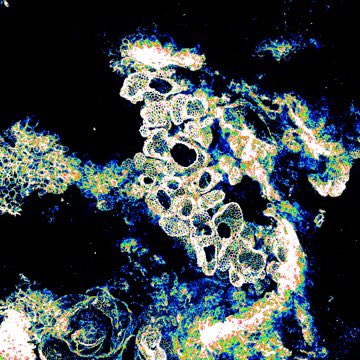

To our collaborators, colleagues and friends, have a very Happy Christmas and wonderful 2024. These festive liver cysts were made by deleting Wdr35 in the bile duct of mice and models PLD. Find out more here: science.org/doi/10.1126/sc… Science Translational Medicine #livertwitter

To our collaborators, colleagues and friends, have a very Happy Christmas and wonderful 2024. These festive liver cysts were made by deleting Wdr35 in the bile duct of mice and models PLD. Find out more here: science.org/doi/10.1126/sc… <a href="/ScienceTM/">Science Translational Medicine</a> #livertwitter